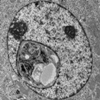

Группа ученых под руководством Рудольфа Джэнича, США, сообщила, что им удалось «перепрограммировать» клетки кожи так, чтобы они облегчали симптомы болезни Паркинсона аналогично стволовым клеткам эмбрионов, проведенные на крысах эксперименты прошли удачно.

Американские ученые разработали свой метод одновременно с японскими около года назад, и уже сейчас их работа дала ощутимые результаты. По мнению исследователей так называемые плюрипотентные стволовые клетки, исходно являющиеся перепрограммированными кожными клетками, идеально подойдут людям с болезнью Паркинсона и другими заболеваниями. А кроме того, это поможет людям, не желающим использовать для своего лечения клетки эмбрионов, рассказывает «Вокруг Света».